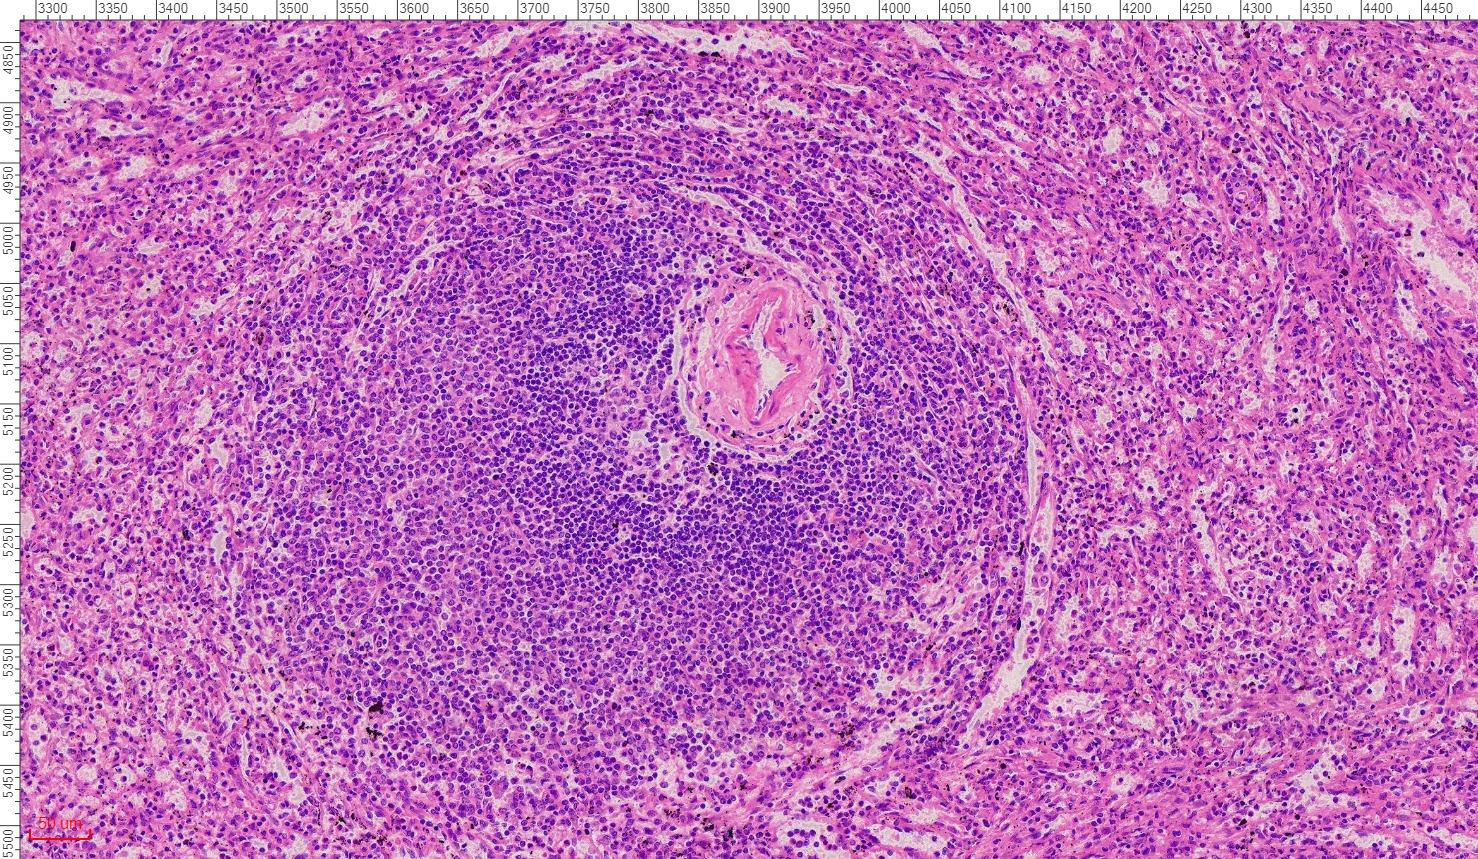

Thickness: 7-micrometer section

Stain: hematoxylin and eosin

Description of the Human spleen section:

- Thickness: 7-micrometer section

- Stain: hematoxylin and eosin

- Show: red pulp, splenic nodule, central artery

Order 10 pieces, we can free send you the scanned 40X digital photos with viewing software.